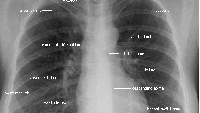

Расшифровка флюорограммы после прохождения флюорографии легких

Описание флюорограммы Результаты флюорографии готовят обычно несколько дней, после этого полученную флюорограмму рассматривает рентгенолог. В том случае, если была проведена флюорография здоровых легких, на дальнейшее обследование пациента не отправляют...